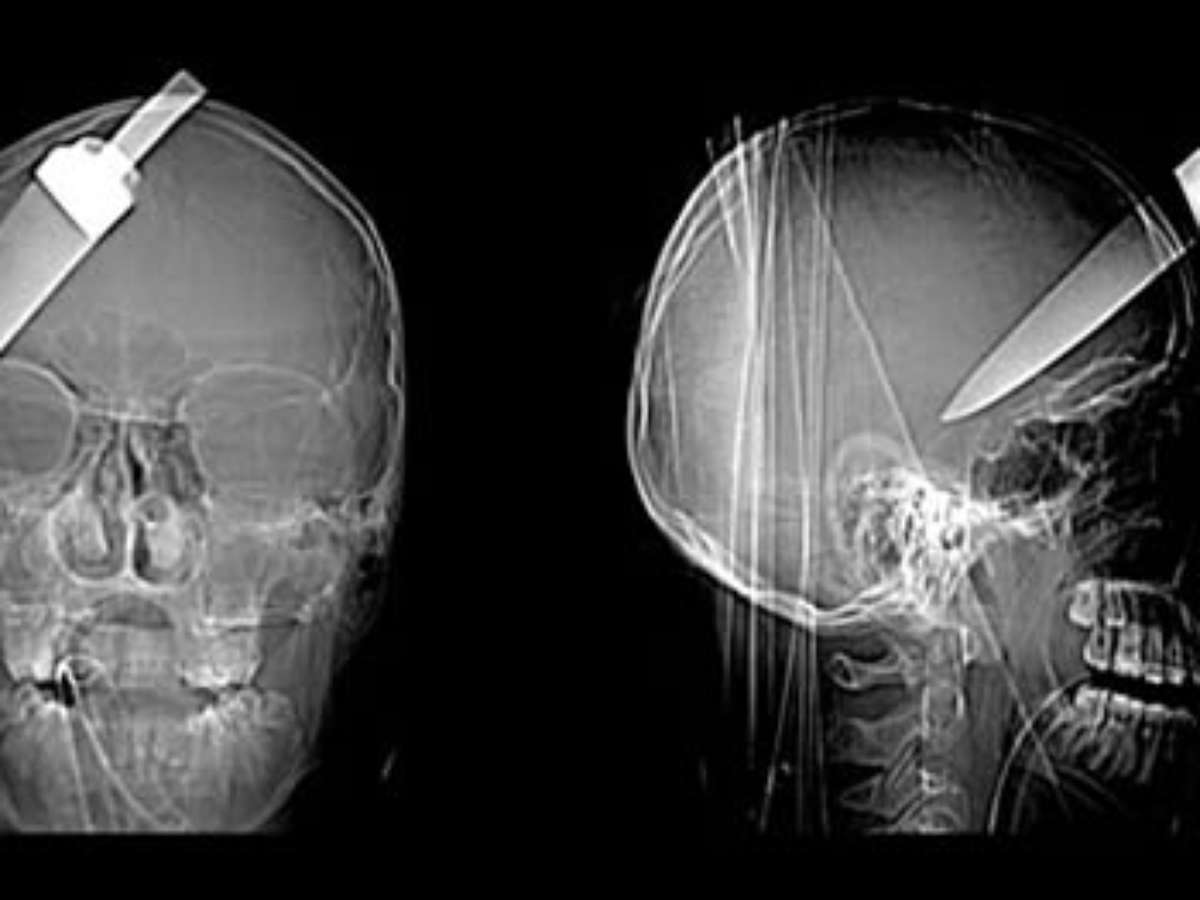

Um adolescente de 16 anos escapou da morte, após ter uma faca de 5 polegadas introduzida em sua cabeça. O jovem foi levado ao hospital com a faca ainda na cabeça